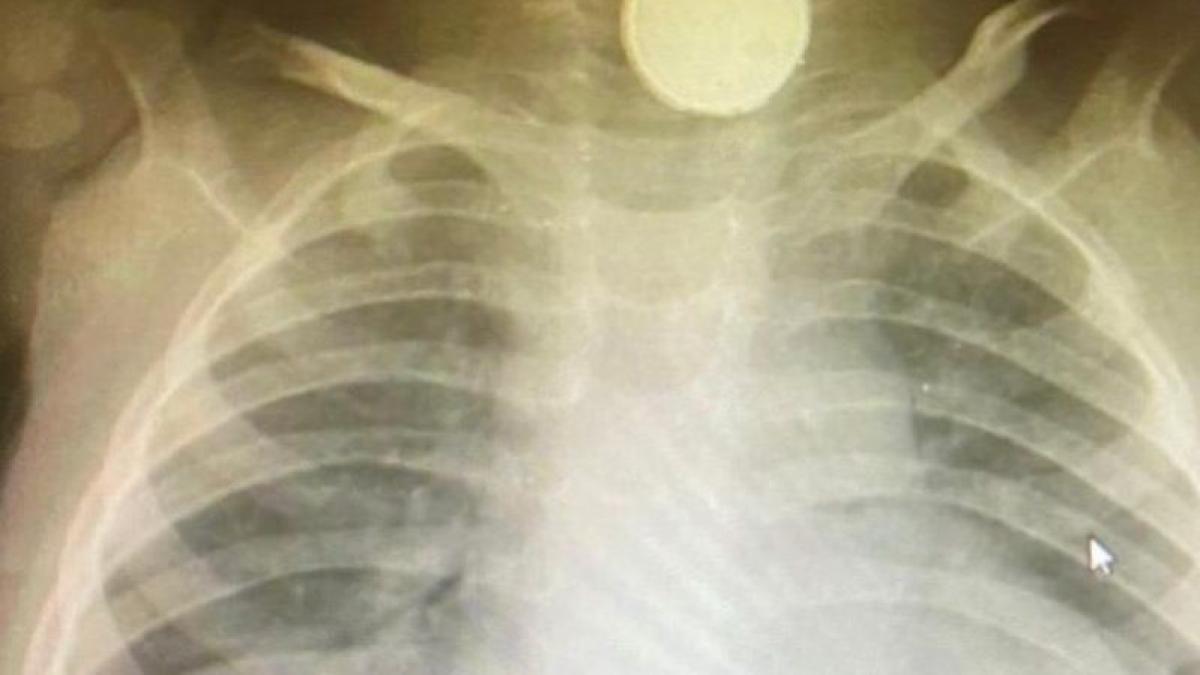

După o vizită la spital în luna mai, o radiografie a dezvăluit că copilul avea o baterie blocată în esofag și aceasta îi afectase puternic gâtul pentru că se corodase. Sofia-Grace Hill a avut un tub introdus în gât pentru a fi hrănită, dar și pentru a preveni sufocarea. La fiecare două săptămâni a fost supusă unei anestezii generale pentru a i se lărgi esofagul, dar este posibil să aibă nevoie de operații și pe viitor.